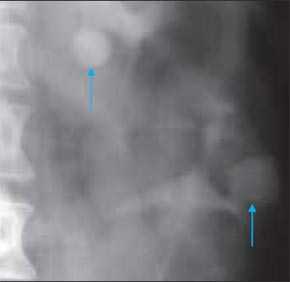

2. Рентгенологические признаки бертиниевых колонн почки:

• Внутривенная пиелография:

о Синдром сдавливания чашечно-лоханочной системы, всегда на уровне отхождения почечной вены

о Скошенность (аномальное разделение) верхнего и нижнего полюсов собирательной системы

Многолетний опыт экскреторной урографии показал, что чашечно-лоханочные системы имеют крайне большое количество вариантов строения. Они практически индивидуальны не только для каждого человека, но и для левой и правой почек у одного субъекта. С развитием и все более широким использованием УЗИ и РКТ, позволяющим прослеживать как внутренние, так и наружные контуры паренхимы почек, на наш взгляд, аналогичное положение складывается и в отношении вариантов анатомического строения паренхимы почек. Сопоставление эхо- и компьютерно-томографических данных с урографическими при различных вариантах псевдоопухолей почек показало, что между анатомическим строением паренхимы и чашечно-лоханочных систем почек имеется взаимосвязь. Она выражается в конгруэнтности медиального контура паренхимы в эхо- или компьютерно-томографическом изображении с латеральным контуром чашечно-лоханочных систем, условно проведенным на экскреторных урограммах или на компьютерных томограммах с контрастным усилением [4, 17, 18]. Этот симптом прослеживается при обычном строении паренхимы и чашечно-лоханочных систем, а также при "перемычке" паренхимы почки, предсталяющей собой вариант анатомического строения. При опухоли почки, являющейся приобретенным патологическим процессом, конгруэнтность контуров паренхимы и чашечно-лоханочных систем почек нарушается (рис. 4).

Рис. 4. Симптом конгруэнтности контуров паренхимы и чашечно-лоханочной системы почки при неполной "перемычке" паренхимы (объяснение в тексте).